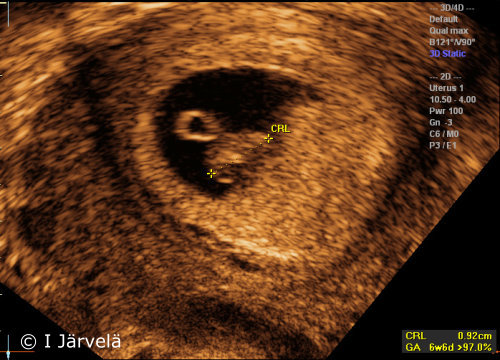

Pregnancy Week 6 (Ultrasound Scan)

Pregnancy week 6 (ultrasound scan). In the 6th week of pregnancy, the crown-rump length (CRL) of the embryo can be measured. The yolk sac can be seen at the side of the embryo.

Picture: Ilkka Järvelä; text: Dimitrios Scordas